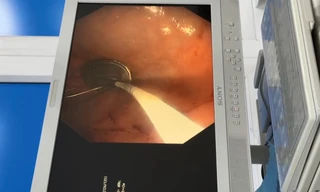

TPO - Trong lúc cả gia đình đang tất bật với công việc ngày cận Tết, bé 5 tuổi đã nuốt cục pin điện tử vào đường tiêu hóa, đối mặt với nguy cơ thủng ruột. Các bác sĩ đã tiến hành nội soi gắp thành công dị vật cho bệnh nhi.